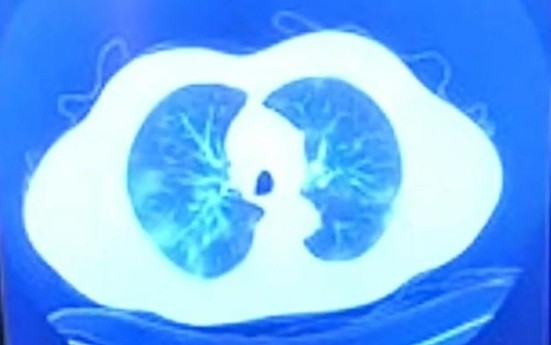

El gobernador estaba acompañado del secretario de Salud estatal, Alonso Pérez Rico, quien explicó que el lunes le detectaron una neumonía por COVID-19 y decidieron hospitalizarlo, especialmente por el riesgo de su edad.

Pérez Rico dijo que Bonilla ya no necesita oxígeno y ha evolucionado "muy favorablemente" en las últimas 48 horas.

Tomografía del lunes 14 que muestra lesiones.

Se determina que presenta neumonía viral.